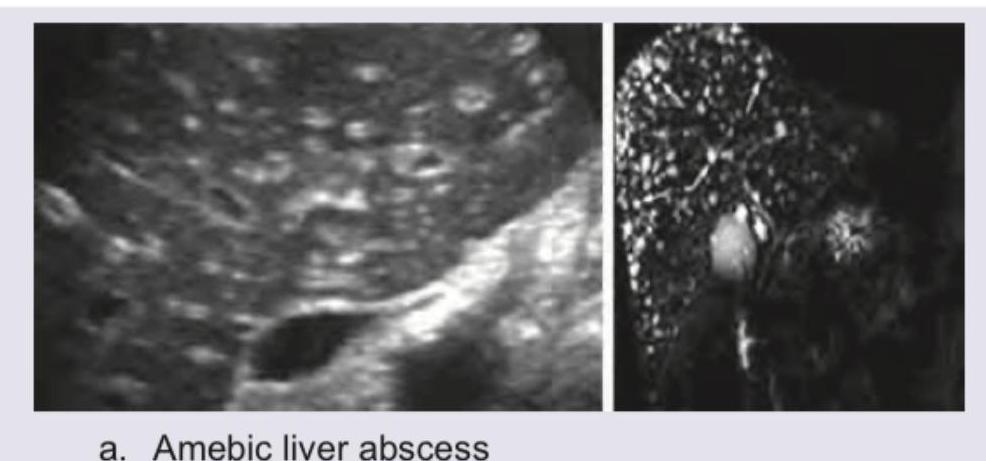

A 48-year-old intravenous drug abuser presents with vomiting, jaundice and right hypochondrium pain. USG abdomen shows presence of:

Explanation: ***Amebic liver abscess*** - The image provided clearly labels "a. Amebic liver abscess" and the clinical presentation of **vomiting**, **jaundice**, **right hypochondrium pain**, and particularly **intravenous drug abuse** (a risk factor for infections, including those that can lead to abscesses) are consistent with a liver abscess. - The ultrasound image (left panel) likely shows a **hypoechoic lesion** within the liver, characteristic of an abscess. The MR image (right panel, likely an MRCP or similar sequence) also shows features consistent with an intrahepatic lesion. *Acute viral hepatitis* - While intravenous drug abuse is a risk factor for **viral hepatitis** (e.g., HBV, HCV), acute viral hepatitis typically presents with diffuse liver inflammation, which would appear as **hepatomegaly** and altered parenchymal echogenicity on ultrasound, rather than a focal lesion like an abscess. - The imaging for acute viral hepatitis usually doesn't show a well-defined **focal lesion** as depicted. *Acute cholecystitis* - **Acute cholecystitis** involves inflammation of the gallbladder, often due to gallstones, presenting with right hypochondrium pain. - The provided images focus on the liver parenchyma and do not specifically show signs like **gallbladder wall thickening**, pericholecystic fluid, or gallstones within the gallbladder, which are characteristic of cholecystitis. *Hepatocellular carcinoma* - **Hepatocellular carcinoma (HCC)** is a primary liver cancer, often seen in patients with chronic liver disease (e.g., from chronic viral hepatitis or alcoholism). - While HCC can present as a focal liver lesion, the clinical context of **acute symptoms** (vomiting, jaundice, pain) and intravenous drug abuse points more towards an infectious process like an abscess rather than a typically more indolent malignant lesion unless there's a specific acute complication.